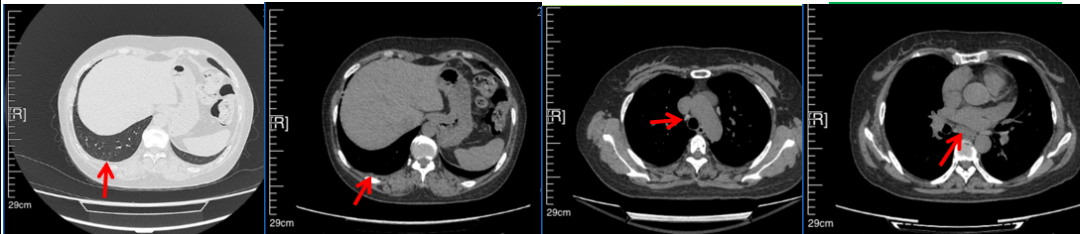

临床诊断:右肺上叶恶性肿瘤rT0N0M1a IVA期(第9版分期);恶性胸腔积液。

诊疗经过:2022年5月始口服克唑替尼3个月,出现肝功能异常(DILI 2级伴临床症状),改用恩沙替尼靶向治疗至今,目前评效为维持PR。恩沙替尼应用期间出现轻度肝功能异常(DILI 1级),对症处理后好转。截止目前PFS 33个月。

2022.08

2023.05

2024.12